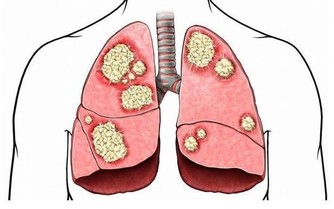

什麼是血管病?

和血管本身有關的疾病,都屬於血管病。

血管病我們可以通俗地理解為身體裡的血液輸送管道出現的問題。

血管就像平時我們見到的自來水管道,血液在管道裡面進進出出,用久了有些管道會生鏽、會堵塞,有些地方會老舊破裂、會扭曲變形。